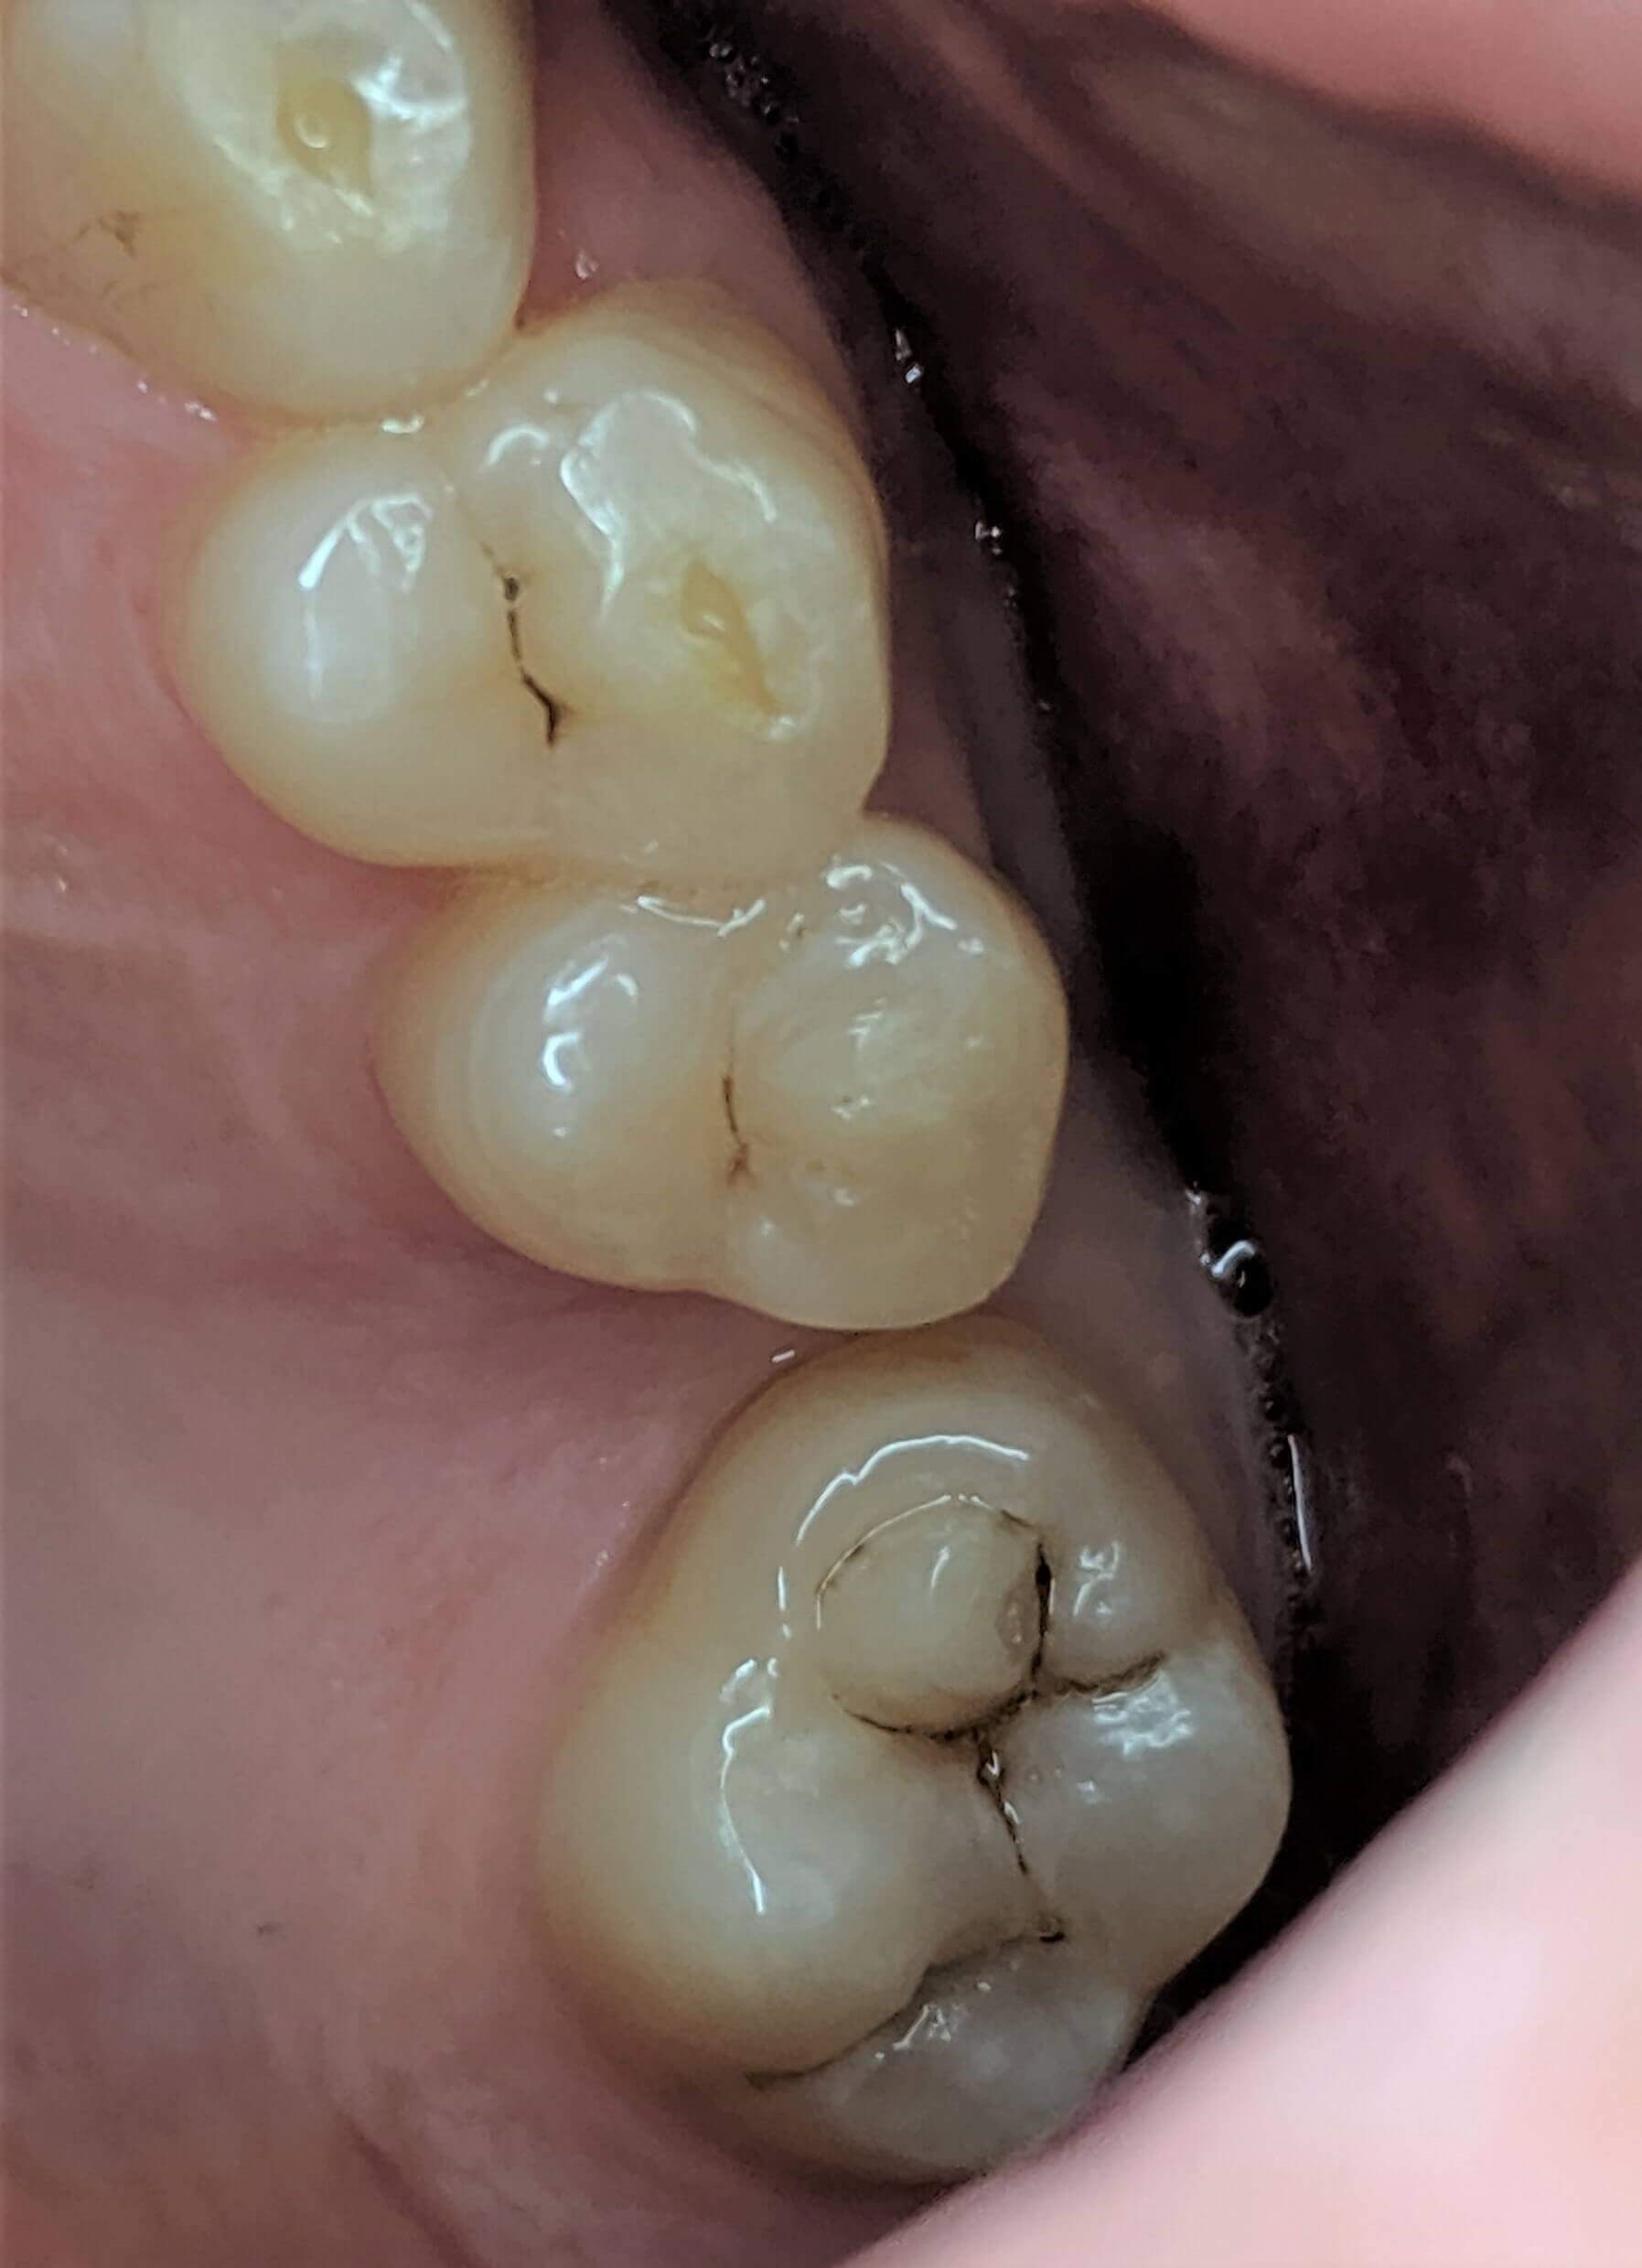

Tooth-colored fillings often fill in the decay in the enamel after it has been cleaned. Composite resin is a versatile material that can be used to treat other problems with your teeth, including cracks or enamel that has been worn down by teeth grinding (bruxism). Since the composite resin is colored to match your natural teeth, tooth-colored fillings can be used on both the front and back teeth for a seamless appearance. If you have metal fillings, talk to Dr. Kim or Dr. Chang about having them removed and replaced with tooth-colored fillings.

Getting a filling at Luminous Dental Studio is typically an easy process. The area surrounding the cavity will be numbed with a local anesthetic to minimize your discomfort. Other forms of sedation can be discussed if you have any fears or dental anxieties to help keep you at ease during the procedure. Once you are prepared, the decayed enamel is removed with a unique dental drill that Dr. Kim or Dr. Chang will select based on where the cavity is located in the tooth and the level of decay. After the enamel is removed and the tooth is cleaned, the cavity will be filled with the composite material and set with a special light. Dr. Kim or Dr. Chang will polish the filling so it feels comfortable and matches your natural teeth.